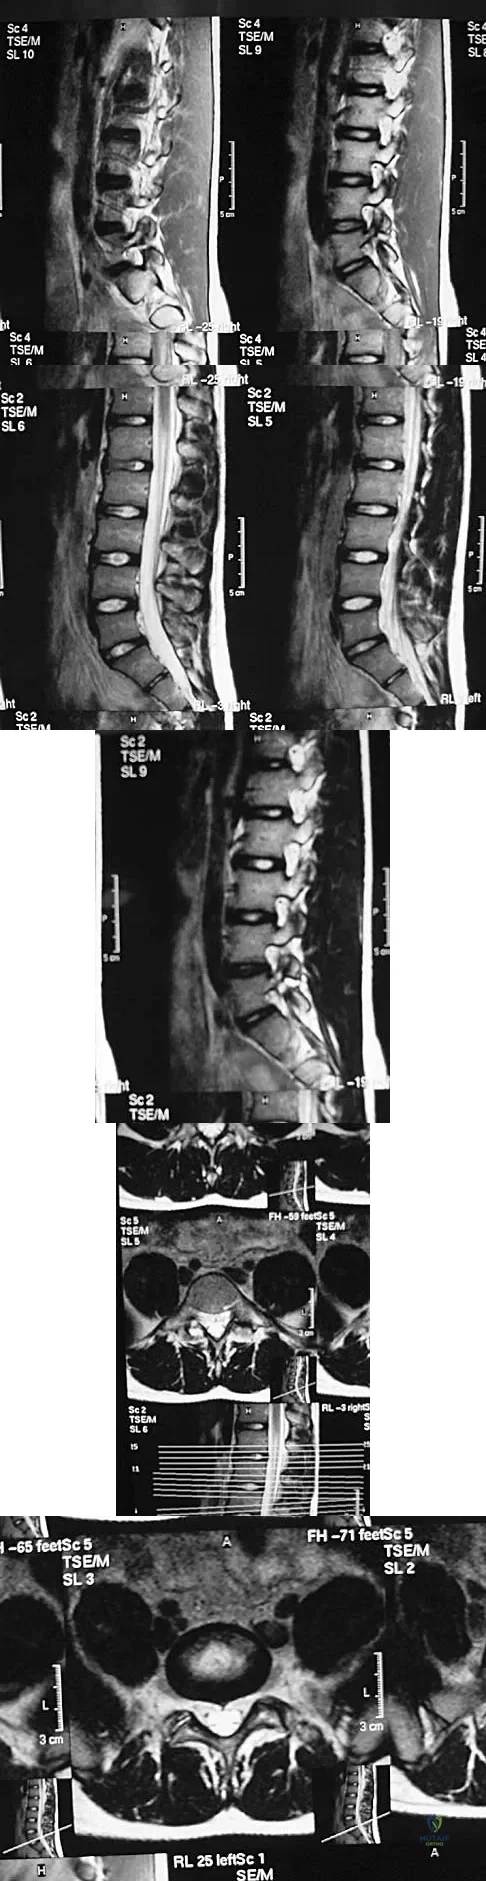

A 45-year-old man seen in the emergency department reports a 1-week history of worsening low back pain and a progressive neurologic deficit in the S1 distribution. Examination reveals 2/5 strength in the gastrocnemius. Laboratory studies show a WBC count of 13,500/mm3 and an erythrocyte sedimentation rate of 74 mm/h. Radiographs of the lumbosacral spine show narrowing of the L5-S1 disk space, with irregularity of the end plates. A sagittal T2-weighted MRI scan is shown in Figure 8. Definitive management should consist of

A 19-year-old man has had back pain with activity, especially running in soccer and baseball, for the past 4 months. He denies any history of trauma. Examination reveals no motor weakness or sensory changes in the lower extremities. Range of motion shows increased pain with extension and mild limitation with flexion. A sitting straight leg raising test is limited at approximately 60 degrees bilaterally by back and buttocks pain. Plain radiographs are normal. MRI scans are shown in Figures 13a through 13e. What is the most likely diagnosis?